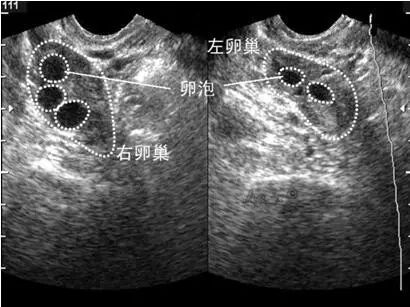

卵泡大于18mm就属于成熟卵泡,正常卵泡直径应在18~25mm之间。卵泡排卵直径是因人而宜的,或因“月”而异的。有的长到直径15mm就排了,有的却要长到25mm。卵泡发育是一个连续的过程,从初级卵泡成长至成熟卵泡可分成8个等级,前5级卵泡生长可能需要2~3个月时间,从第6级卵泡长大到第8级卵泡一共是10天左右的时间,正好就是一个月经周期中的卵泡期。

图2:B超下卵泡监测